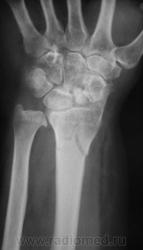

оскольчатый перелом метадиафиза лучевой кости, перелом ладьевидной кости

перелом ладьи старый в ложном суставе, выраженный, посттравматический деф.артроз л\зап сустава, ну и свежий перелом дистального метадиафиза луча, руке где то нужно сгибаться-разгибаться